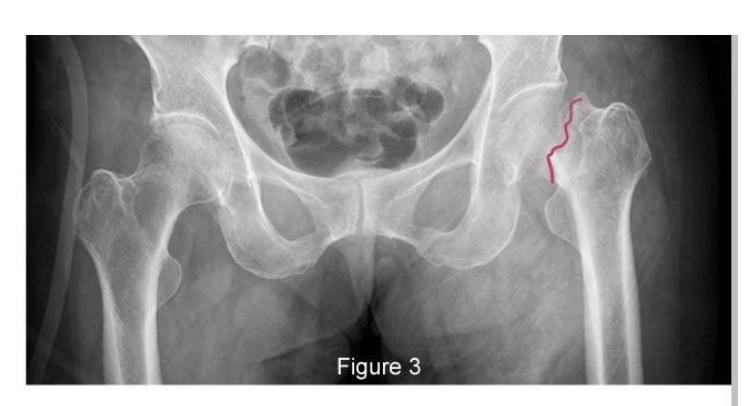

A teenager with acute onset of pain in the right hip during a run. He sustained the injury seen in the x-rays with a white arrow. This injury usually occurs due to a forceful eccentric contraction of which of the following muscles?

- C. Rectus femoris

- Sartorius

Pelvic Anatomy

Which of the following muscles is attached to the structure pointed by the arrow?

- C. Sartorius

Note: Arrow was pointing at ASIS (Anterior Superior Iliac Spine)